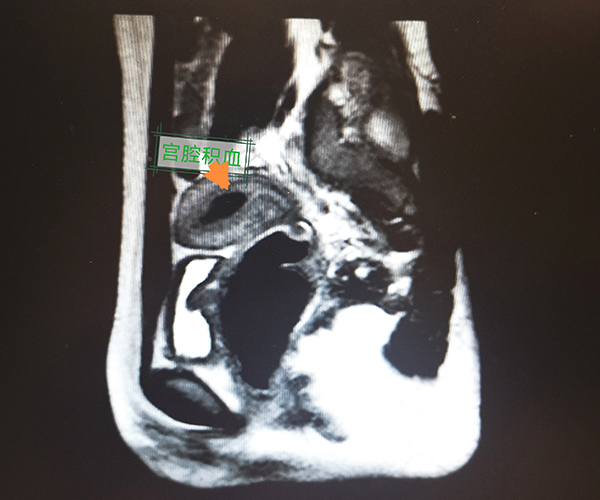

經過一番解釋,媽媽和孩子對疾病有了了解,決定進行手術治療。楊嵐副主任醫師對該類疾病有著豐富的臨床經驗,經過認真地查體和磁共振影像評估,她帶領團隊制定了周詳的手術計劃,最終成功為小龍實施了“陰道成形術+陰道斜隔切除術”。打開了封閉的隔墻,約500ml粘稠的積血“奔涌而出”,仔細“拆除”了圍墻后,宮腔鏡檢查雙側宮頸形態和宮腔都恢復正常,手術取得了滿意的效果。